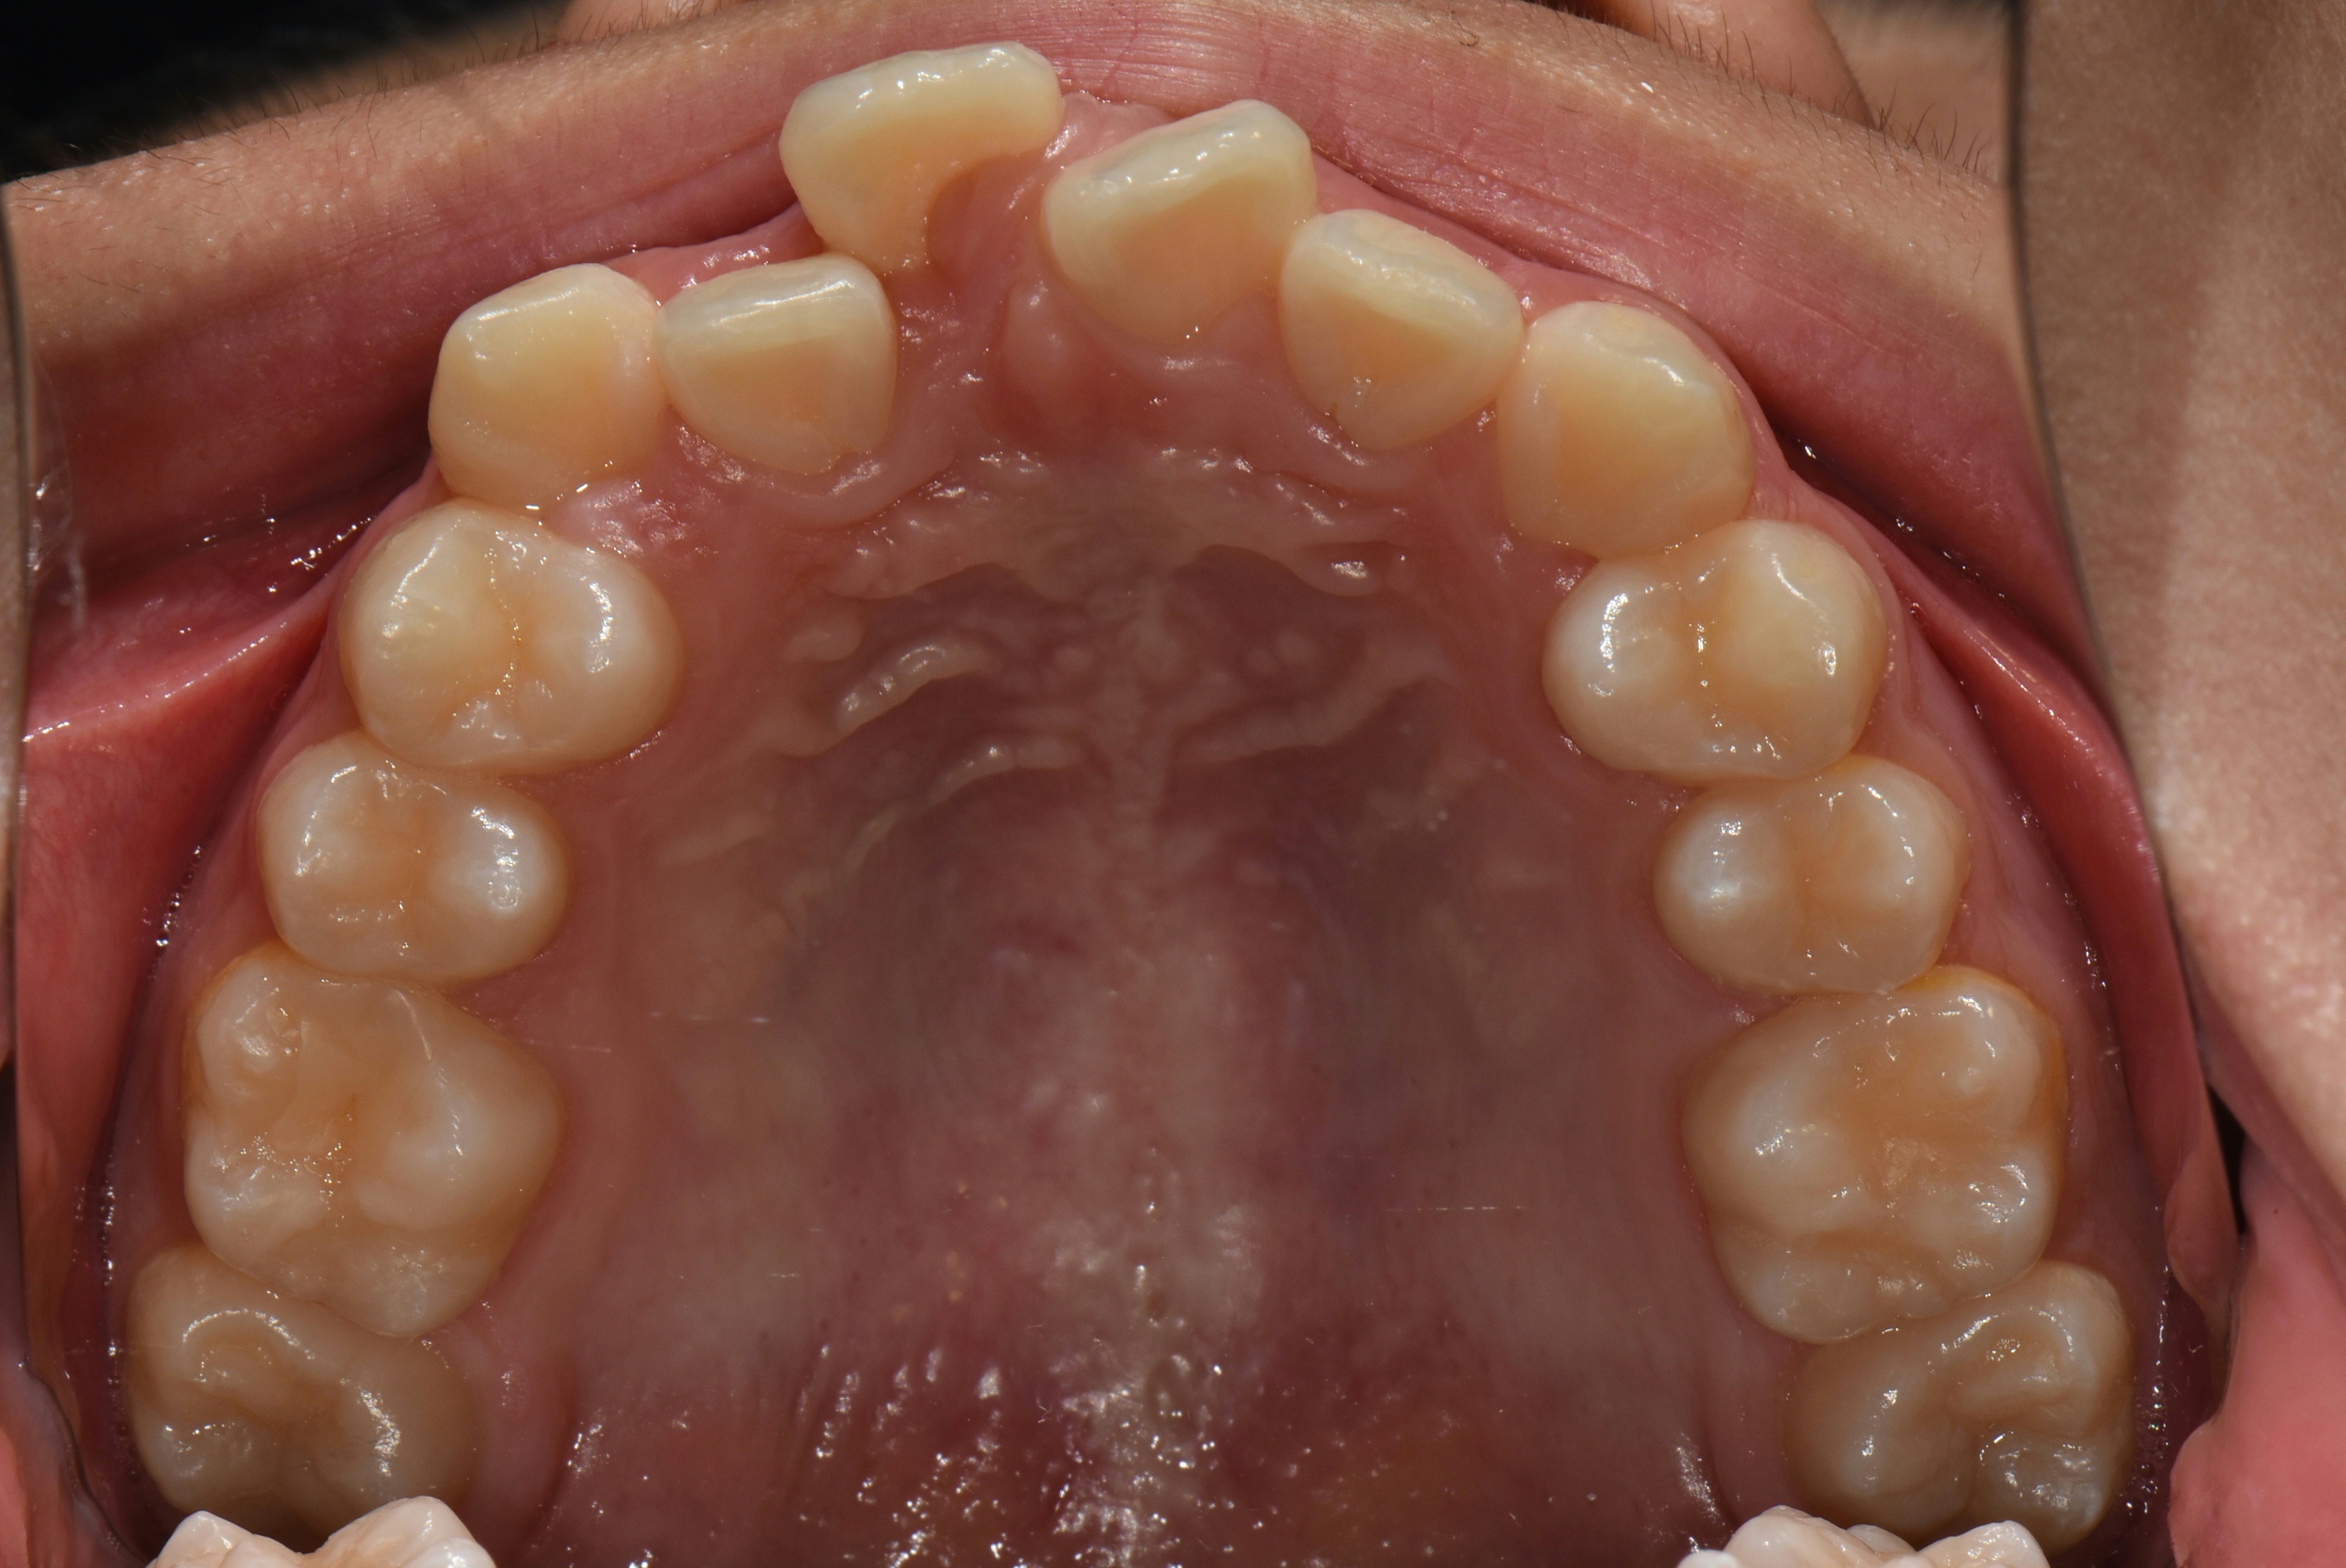

치료 전 사진입니다.